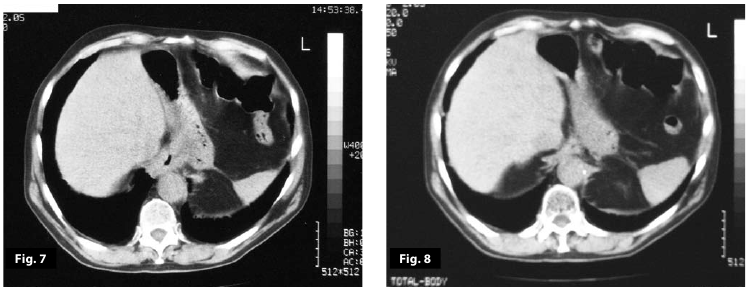

Figure7

Figure8

Figure7-8

Figure5-6-7-8